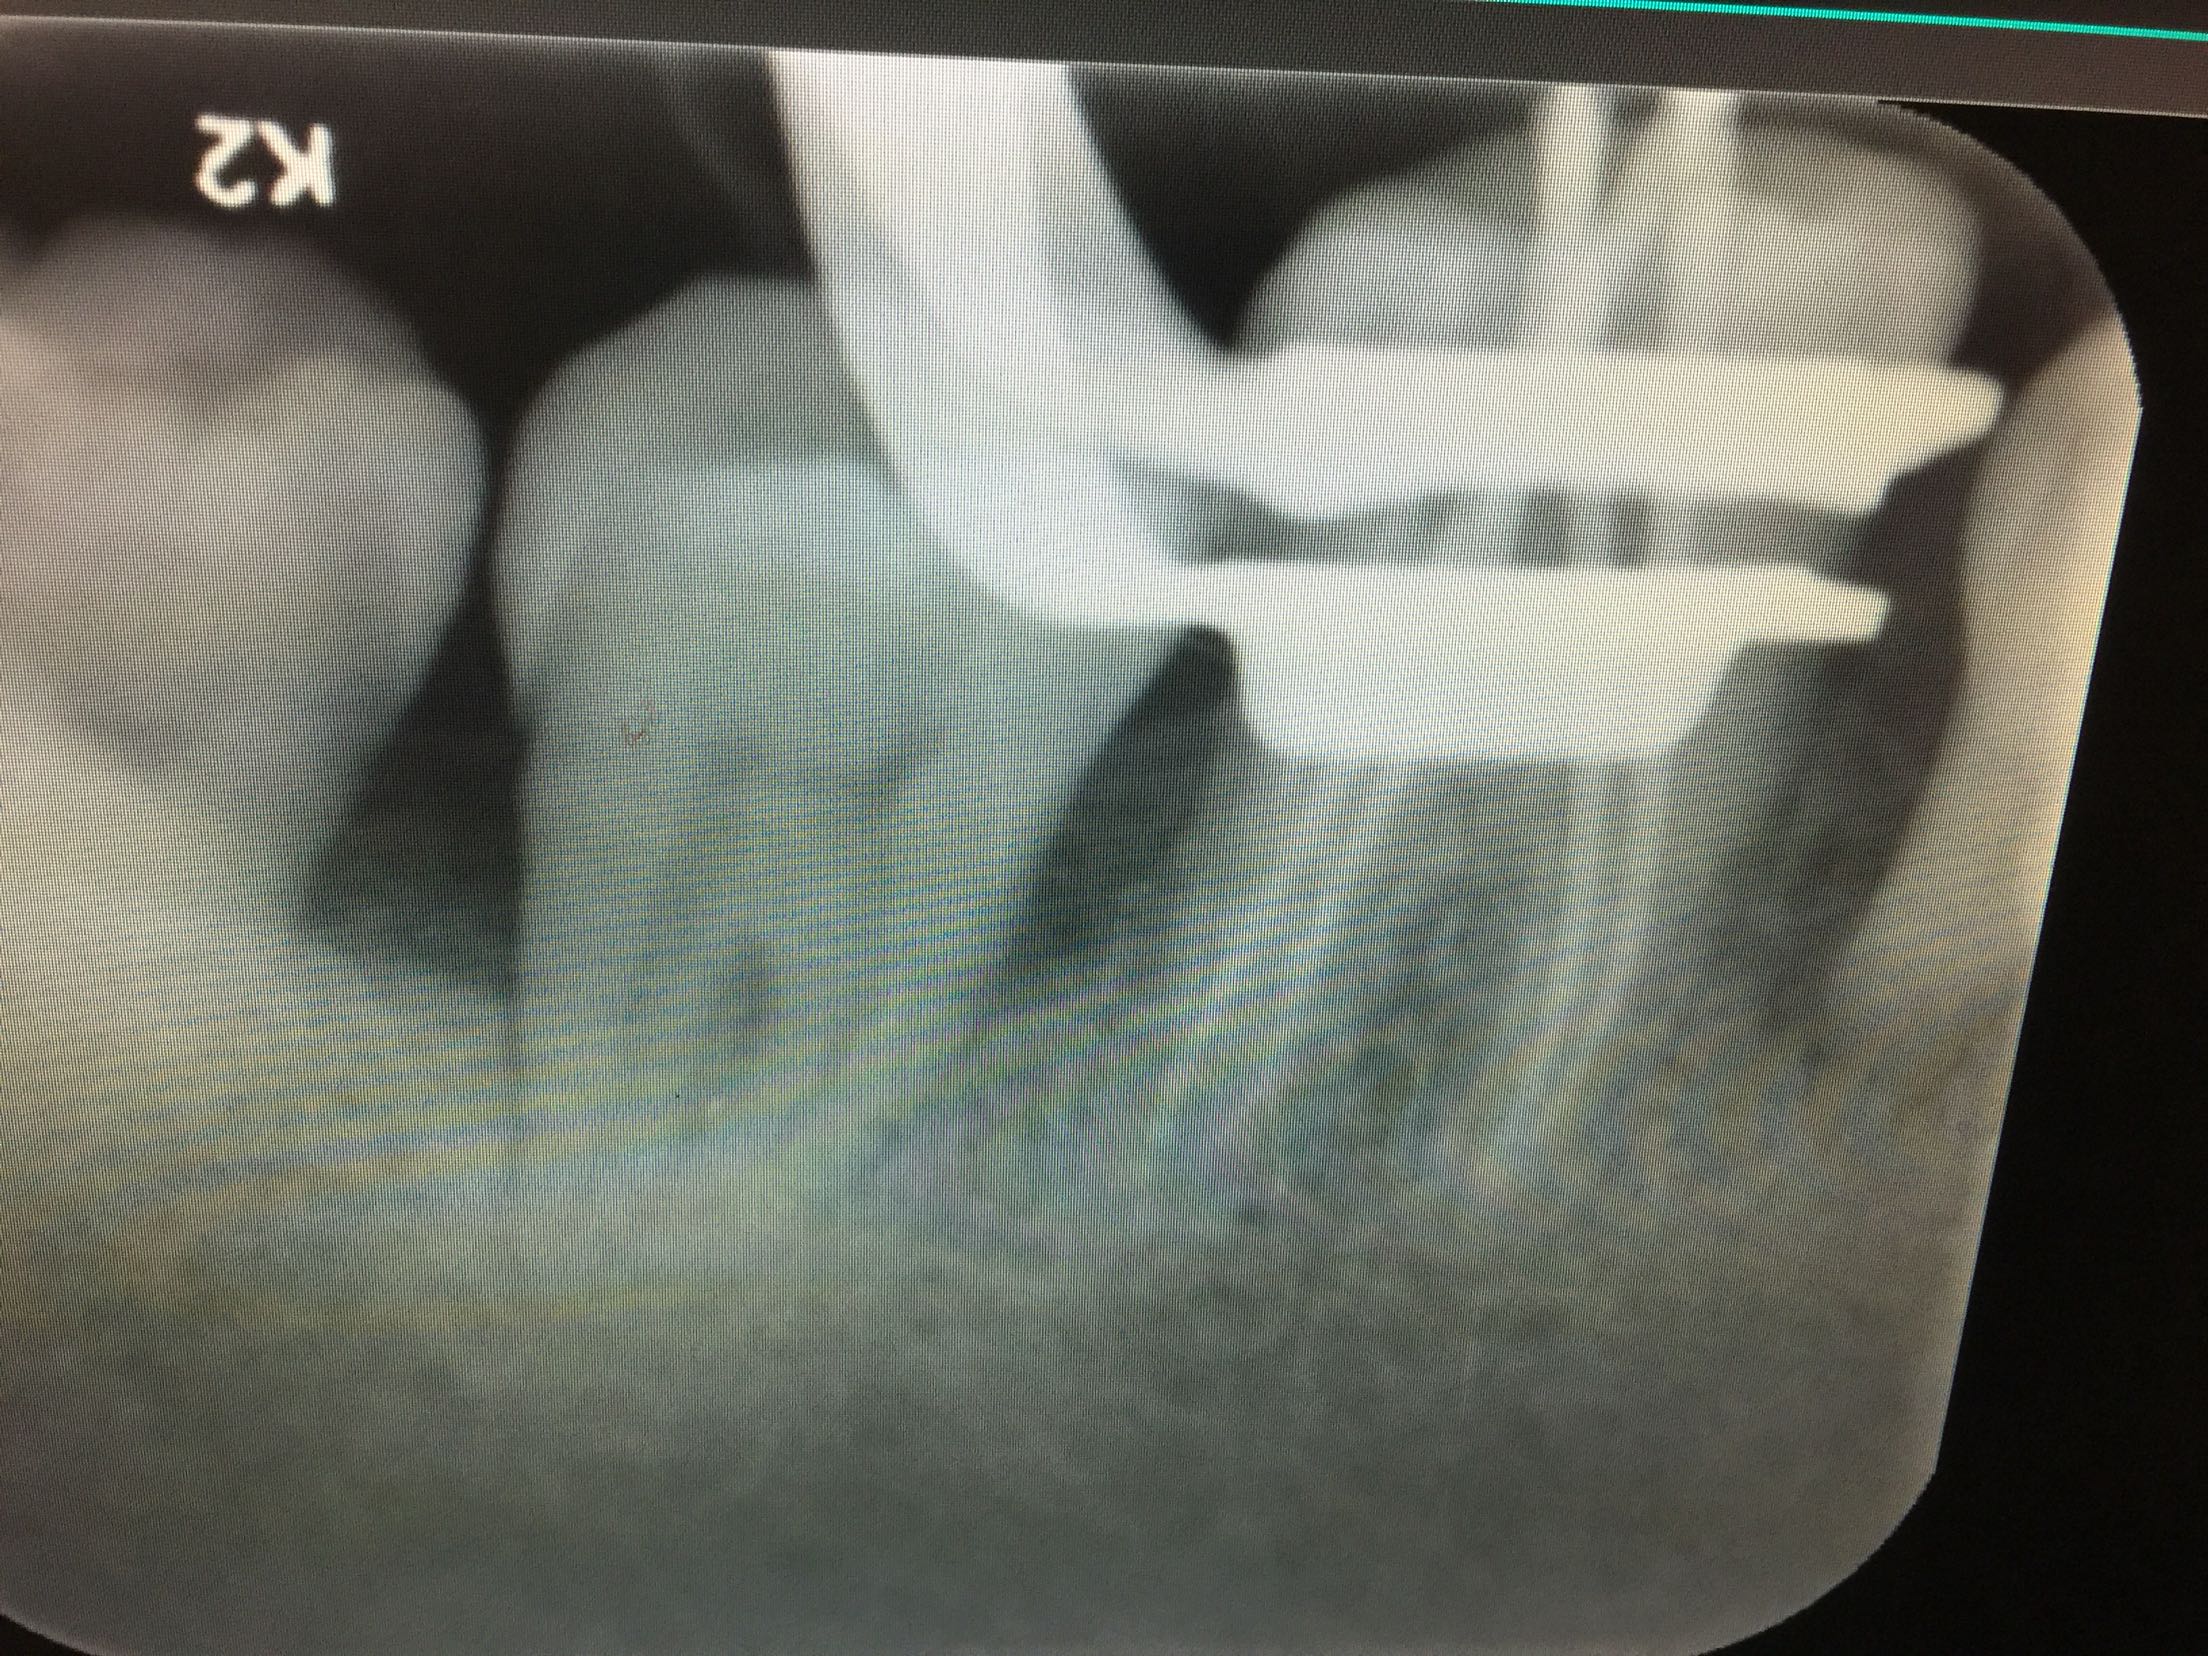

诊断:46牙伸长 全口牙周炎 牙列缺损 治疗计划:46牙去髓术 全口洁治 择期修复缺牙区 治疗:碧蓝麻局部浸润,46牙去净龋坏,开髓揭髓顶,探查根管4根,牙髓摘除术,k挫初步预备,根管测长仪测量根管长度,各根管内导入根管润滑剂EDTA,Protaper镊钛器械预备根管,冲洗,超声荡洗,水溶性氢氧化钙充填根管,暂封,约复诊。 复诊:一周后,诊间无不适,46牙暂封完好,冷-,探-,叩-,不松。 试主尖,

根充